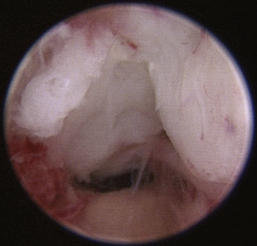

Normal turbinates have a smooth, pink-to-white surface and a spatial alignment that provides channels for the passage of air. The color varies and appears tan in the caudal nasal cavity. Turbinates come in different shapes and sizes, but the surface should be smooth. Ethmoid turbinates in the caudal nasal cavity will have a characteristic stippled or corrugated appearance (Figures 19-13 through 19-16). Ulcerations or various proliferations of the mucosa are indicative of disease. These changes are typically diffuse and accompanied by a lot of mucus. Mucus can be thin to purulent. Copious amounts can be flushed out of the nasal cavity to allow better visibility. The specific disease is determined by biopsy. After full examination of the nasal cavity, run the scope along the floor of the nasal sinus to the level of the choanae. Keeping the scope pointed in a ventral medial direction prevents inadvertent trauma or penetration of the cribriform plate. The index finger of the free hand can be used to follow the scope as it moves caudally over the hard palate; the surgeon can then palpate the scope through the soft palate when it moves into the nasopharynx. Some force is needed to complete this procedure and may result in increased bleeding.

image

Figure 19-13 Normal canine rostral nasal cavity; the septum is medial (left).